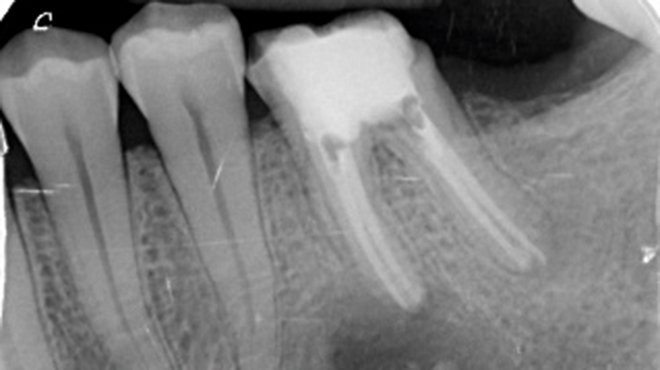

Termín chirurgická endodoncie označuje obor stomatologie, který se zabývá diagnostikou a léčbou lézí endodontického původu, jež nedostatečně reagují na konvenční endodontické ošetření nebo je nelze konvenční cestou ošetřit vůbec.¹ Cílem chirurgické endodoncie je dosažení trojrozměrného vyčištění, opracování a zaplnění apikální části kořenového kanálkového systému, která není přístupná běžným ortográdním přístupem dřeňovou dutinou, ale pouze po odklopení chirurgického laloku (obr. 1.1).

Úspěšnost nechirurgického ošetření kořenových kanálků je vysoká; nicméně nedostatečné zaplnění a utěsnění anatomických složitostí zásadně ovlivňuje dlouhodobý úspěch endodontické léčby.